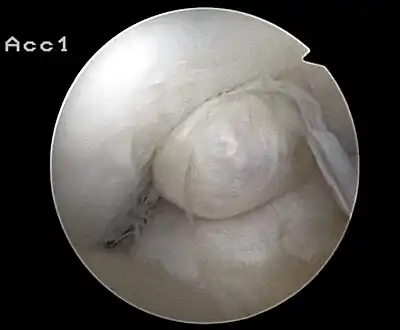

Arthroscopie diagnostique

La sécurité diagnostique la meilleure est obtenue par arthroscopie diagnostique. Ce procédé représente l'étalon-or pour le diagnostic de la rupture de LC. Ce procédé relève d'une chirurgie invasive au minimum, mais comporte certains risques, comme toute intervention chirurgicale dans le genou du patient[113]. Comme cependant le traitement chirurgical d'une rupture de LC sera conduit par chirurgie arthroscopique, il est possible d'enchaîner celle-ci immédiatement après l'arthroscopie diagnostique, par la résection partielle du ligament (pour une déchirure) ou la reconstruction en cas d'arrachement. Avec l'accroissement de la facilité de l'IRM, le nombre d'arthroscopies purement diagnostiques a nettement diminué ces dernières années[114],[115]. L'arthroscopie diagnostique est quand même utilisée comme précédemment comme procédé de choix pour une compréhension certaine du diagnostic de rupture de LC, en cas d'examen clinique confus et d'IRM difficile à interpréter[113].